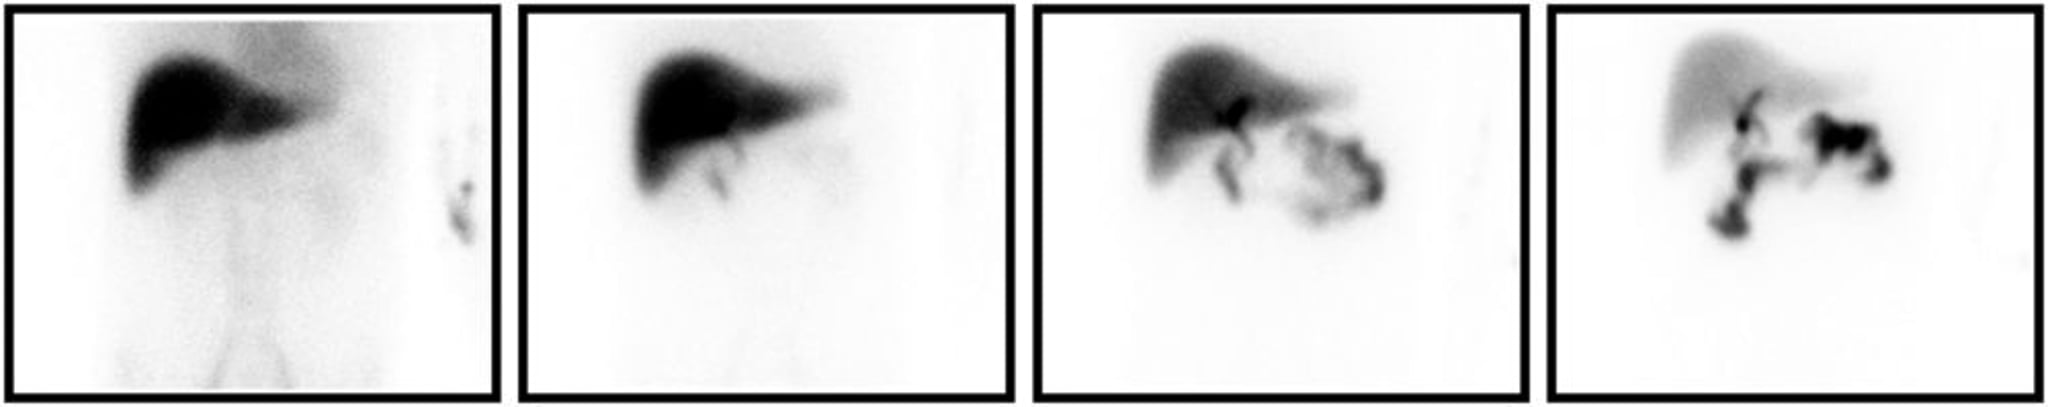

Chụp HIDA

Chụp HIDA thích hợp với viêm túi mật. Hiển thị từ trái qua phải là những ảnh thu được ở 5, 15, 30, và 60 phút sau khi tiêm chất phóng xạ đánh dấu. Thậm chí ở những thời điểm muộn, không có túi mật.